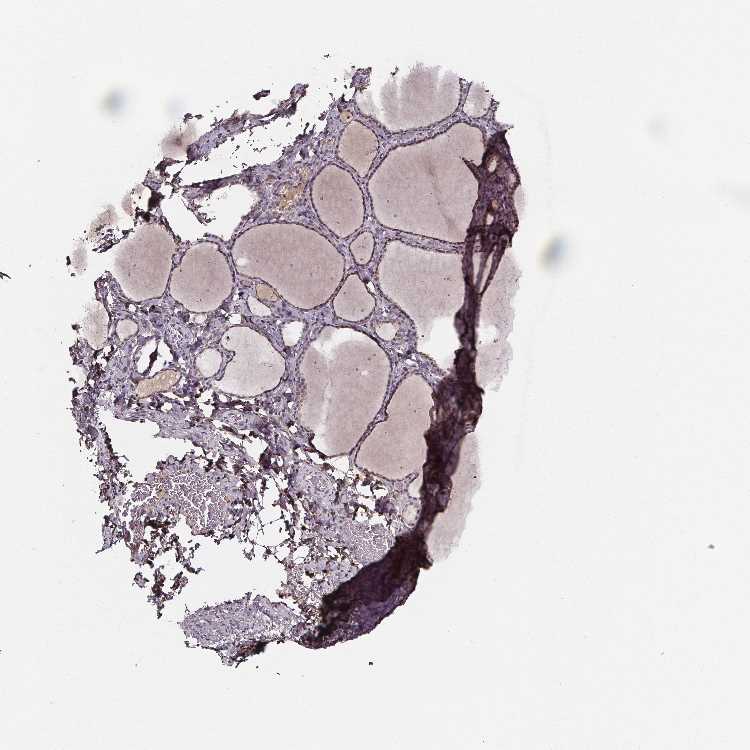

TISSUE PRIMARY DATA THYROID GLAND Show tissue menu

THYROID GLAND - Antibody stainingi

Antibody staining in the annotated cell types in the current human tissue is reported as not detected, low, medium, or high, based on conventional immunohistochemistry profiling in selected tissues. This score is based on the combination of the staining intensity and fraction of stained cells.

Each image is clickable and will lead to virtual microscopy that enables deeper exploration of all samples and also displays staining intensity scores, fraction scores and subcellular localization as well as patient and tissue information for each sample.

Antibody HPA068012

Glandular cells Medium